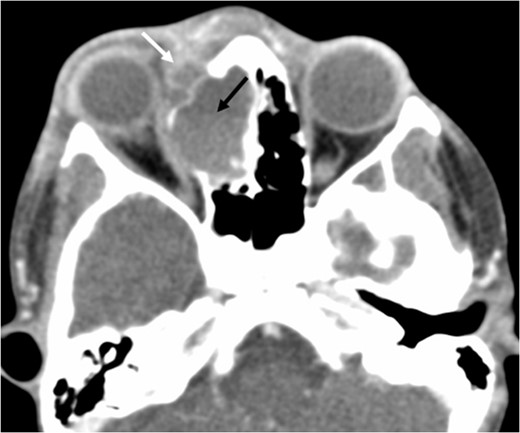

A 6-year-old boy with a background of asthma presented to a tertiary paediatric unit in May 2016 with a 3-day history of right eye pain, proptosis and erythema under the care of the ENT team. A provisional diagnosis of a periorbital cellulitis was made secondary to ethmoid sinusitis and management with intravenous antibiotics (ceftriaxone), intranasal steroids, saline douches and topical oxyxlometazoline was initiated. Ophthalmological assessment demonstrated normal colour vision, acuity and light reflexes bilaterally but also proptosis-related ophthalmoplegia. Computed tomography (CT) imaging of the orbits and paranasal sinuses demonstrated complete opacification of the right-sided paranasal sinuses and compromise of the right frontal and ostiomeatal unit. In addition there was an expansile abnormality centred on the ethmoidal labyrinth with bony remodelling of the lamina papyracea and a subperiosteal collection adjacent to the medial orbital wall (Figs 1 and 2). The most likely diagnosis was felt to be an infective process with mucopyocele formation complicated by a subperisoteal post-septal collection. An MRI scan with gadolinium of the orbits and sinuses confirmed the unilateral pattern of sinus opacification within the right frontal, ethmoids and maxillary sinus. The lesion demonstrated multiple fluid–fluid levels and peripheral enhancement (Figs 3 and 4). The patient was treated by endoscopic drainage of the lesion, which revealed only blood. He initially had some improvement of his proptosis but recurred within a few days and so further, more extensive endoscopic debridement was performed.

Axial non-contrast CT demonstrating an expansile lesion centred on the right-sided ethmoidal labyrinth (long white arrow) with remodelling of the lamina papyracea (short white arrows).

Axial post-contrast CT demonstrating the peripherally enhancing right-sided intra-orbital subperiosteal component. The expansile lesion centred on the right ethmoidal labyrinth demonstrates a faint fluid–fluid level.